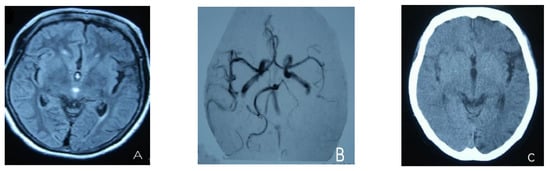

At the age of 51, she had a migraine attack with weakness in the left limb. The headache became increasingly serious, so she was admitted to a hospital six days after the attack. Upon admission, she had severe headaches and left limb weakness, and the neurological examination revealed left hemiparalysis with muscle strength at 3/5 by manual muscles testing (MMT). A brain MRI (magnetic resonance imaging) on day two of admission revealed cortical swelling in the right cerebral hemisphere (Figure 1A), and on the day three of admission, the magnetic resonance angiography (MRA) showed a slight decrease in the branches of the left middle cerebral artery (MCA). The main trunk of the left posterior cerebral artery (PCA) was slender contralateral, and its branches were significantly reduced contralaterally (Figure 1B). Symptoms persisted. On day five of admission, the patient had a focal epileptic seizure, which was followed by two more seizures. Subsequently, the patient’s left limb weakness gradually worsened, the neurologic examination revealed left hemiparalysis with muscle strength at 0/5 by MMT, and she gradually developed unconsciousness to light coma. Brain CT scans during coma revealed swelling of the right cerebral cortex (Figure 1C). Contrast-enhanced brain MRI showed swelling and diffuse enhancements in the cortex of the right cerebral hemisphere (Figure 1D). Perfusion-weighted imaging (PWI) showed right hemisphere hyperfusion (Figure 1E). Based on her medical history and presentation at admission, a lumbar puncture was performed, and the cerebrospinal fluid pressure (CSF) was 204 mm H2O. The biochemical and cytologic examination of the CSF revealed normal chloride, glucose and cell counts and classifications, in addition to normal protein levels. The CSF tested negative for bacteria, viruses, fungi and autoimmune encephalitis. Whole-exome sequencing showed a missense mutation (c.2473G > A, p.Glu825Lys) in exon 18 of ATP1A2. Based on a series of tests, the patient was diagnosed with FHM2 caused by a pathogenic ATP1A2 mutation. During hospitalization, we dehydrated the patient, gave the patient paracetamol for symptomatic treatment and an intramuscular injection of phenobarbital to control seizures. On the 15th day after admission, consciousness and hemiplegia improved, and the headache was relieved; the patient was discharged after 22 days. She was back to normal, and at later follow-up, the patient’s brain MRI (Figure 2A), contrast-enhanced brain MRI (Figure 2B), PWI (Figure 2C) and computed tomography angiography (CTA) all returned to normal (Figure 2D). The time course diagram of the disease in our patient is presented in Figure 3.

Figure 1.

(A) Cortical swelling in the right cerebral cortex (the 2nd day); (B) the MCA and PCA branches decreased (the 3rd day); (C) swelling of right cerebral cortex (the 7th day); (D) swelling and diffuse enhancement in the cortex of the right cerebral hemisphere; (E,F) right hemisphere hyperfusion.